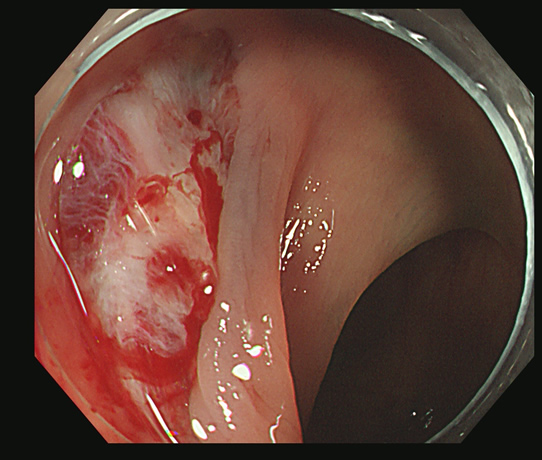

切除創に白い突起(CSDP)があり、よく見ると根本に粘膜の遺残が見られます

切除創を時間をかけて丁寧に観察することが重要です

これをカンシで大きくつかみ取ります